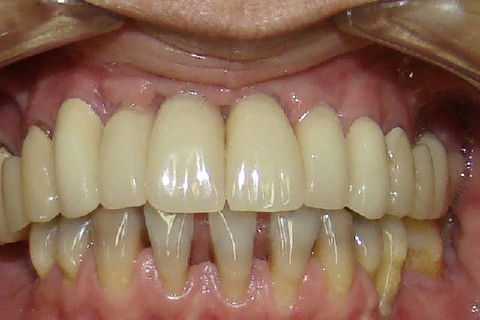

Finalização do tratamento reabilitador, com coroas metalo-ceramicas superiores e coroas unidas no lado direito da mandibula e unitaria da lado esquerdo

Sorriso final da paciente

Paciente portadora de reabilitação superior com protese fixa ferulizada e diastemas nos incisivos inferiores, procurou tratamento para "individualizar"os dentes, principalmente os superiores. No planejamento ficou estabelecido que seriam feitos enxertos de elevação do soalho do seio maxilar bilateral e enxertos em bloco na região anterior da maxila. Na mandibula tratamento ortodontico. Após o periodo de cicatrização dos enxertos, implantes foram colocados na maxila. Na mandibula após o termino do tratamento ortodontico, foram colocados implantes. Proteses temporarias foram instaladas e acompanhadas por 6 meses e então feram feitas as reabilitações proteticas superiores e inferiores.